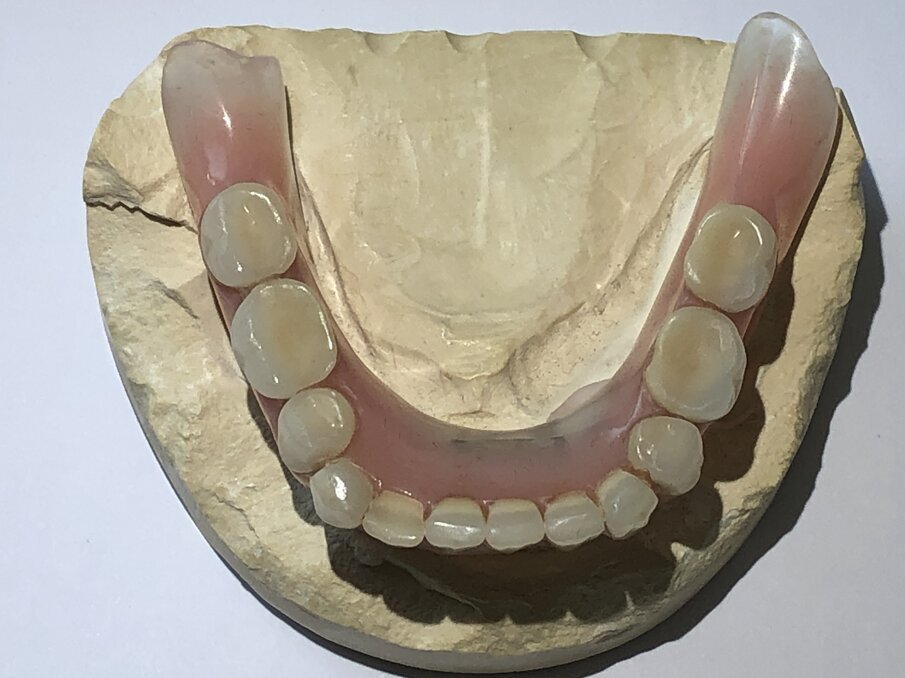

Het gehele secundaire deel in de prothese zit op de staaf met behulp van de gefreesde kunststofonderdelen en zorgt voor een comfortabele grip van de prothese. Om de houvast van de prothese te versterken, worden er ook nog twee kunststof precisie-onderdelen distaal in het gefreesde kunststof deel ingebracht (afbeelding 10, het gele gedeelte). In vergelijking met de klassieke staafconstructie zorgt deze innovatieve constructie ervoor dat de prothese een stevige houvast heeft, zodat de patiënt soepel en moeiteloos in alles kan bijten.

De nieuwe gemodificeerde staafconstructie zorgt voor een uitzonderlijke, ingenieuze houvast van de prothese in de edentate kaak. Deze unieke constructie is niet te vergelijken met de huidige staafconstructies. In appels en wortels bijten is voor patiënten met deze nieuwe constructie net zo eenvoudig als het eten van een stuk taart.

Dankzij onze nieuwe werkwijze worden de protheseranden sierlijker, welgevormder en vanzelfsprekend in de bovenkaak gehemeltevrij. In tegenstelling tot de standaardconstructie waarbij drukpunten ontstaan door minimale bewegingen, is dat in deze nieuwe constructie niet het geval. Het kunststofgedeelte in het secundaire gedeelte van de prothese kan indien nodig zonder veel moeite worden vervangen.